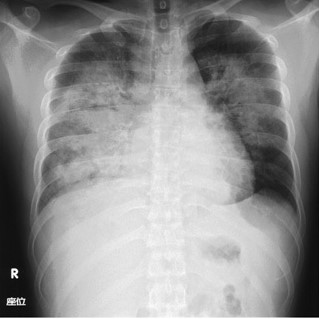

@肺炎

一般細菌としては(マイコプラズマやクラミジア、ウイルスを除けば)、市中肺炎の最大の起炎菌です。

乳幼児ではインフルエンザ桿菌に次いで多い起炎菌です。

また、乳幼児では全身性感染症の部分症状として肺炎が発症する場合があります。

鉄錆色の喀痰を示します。